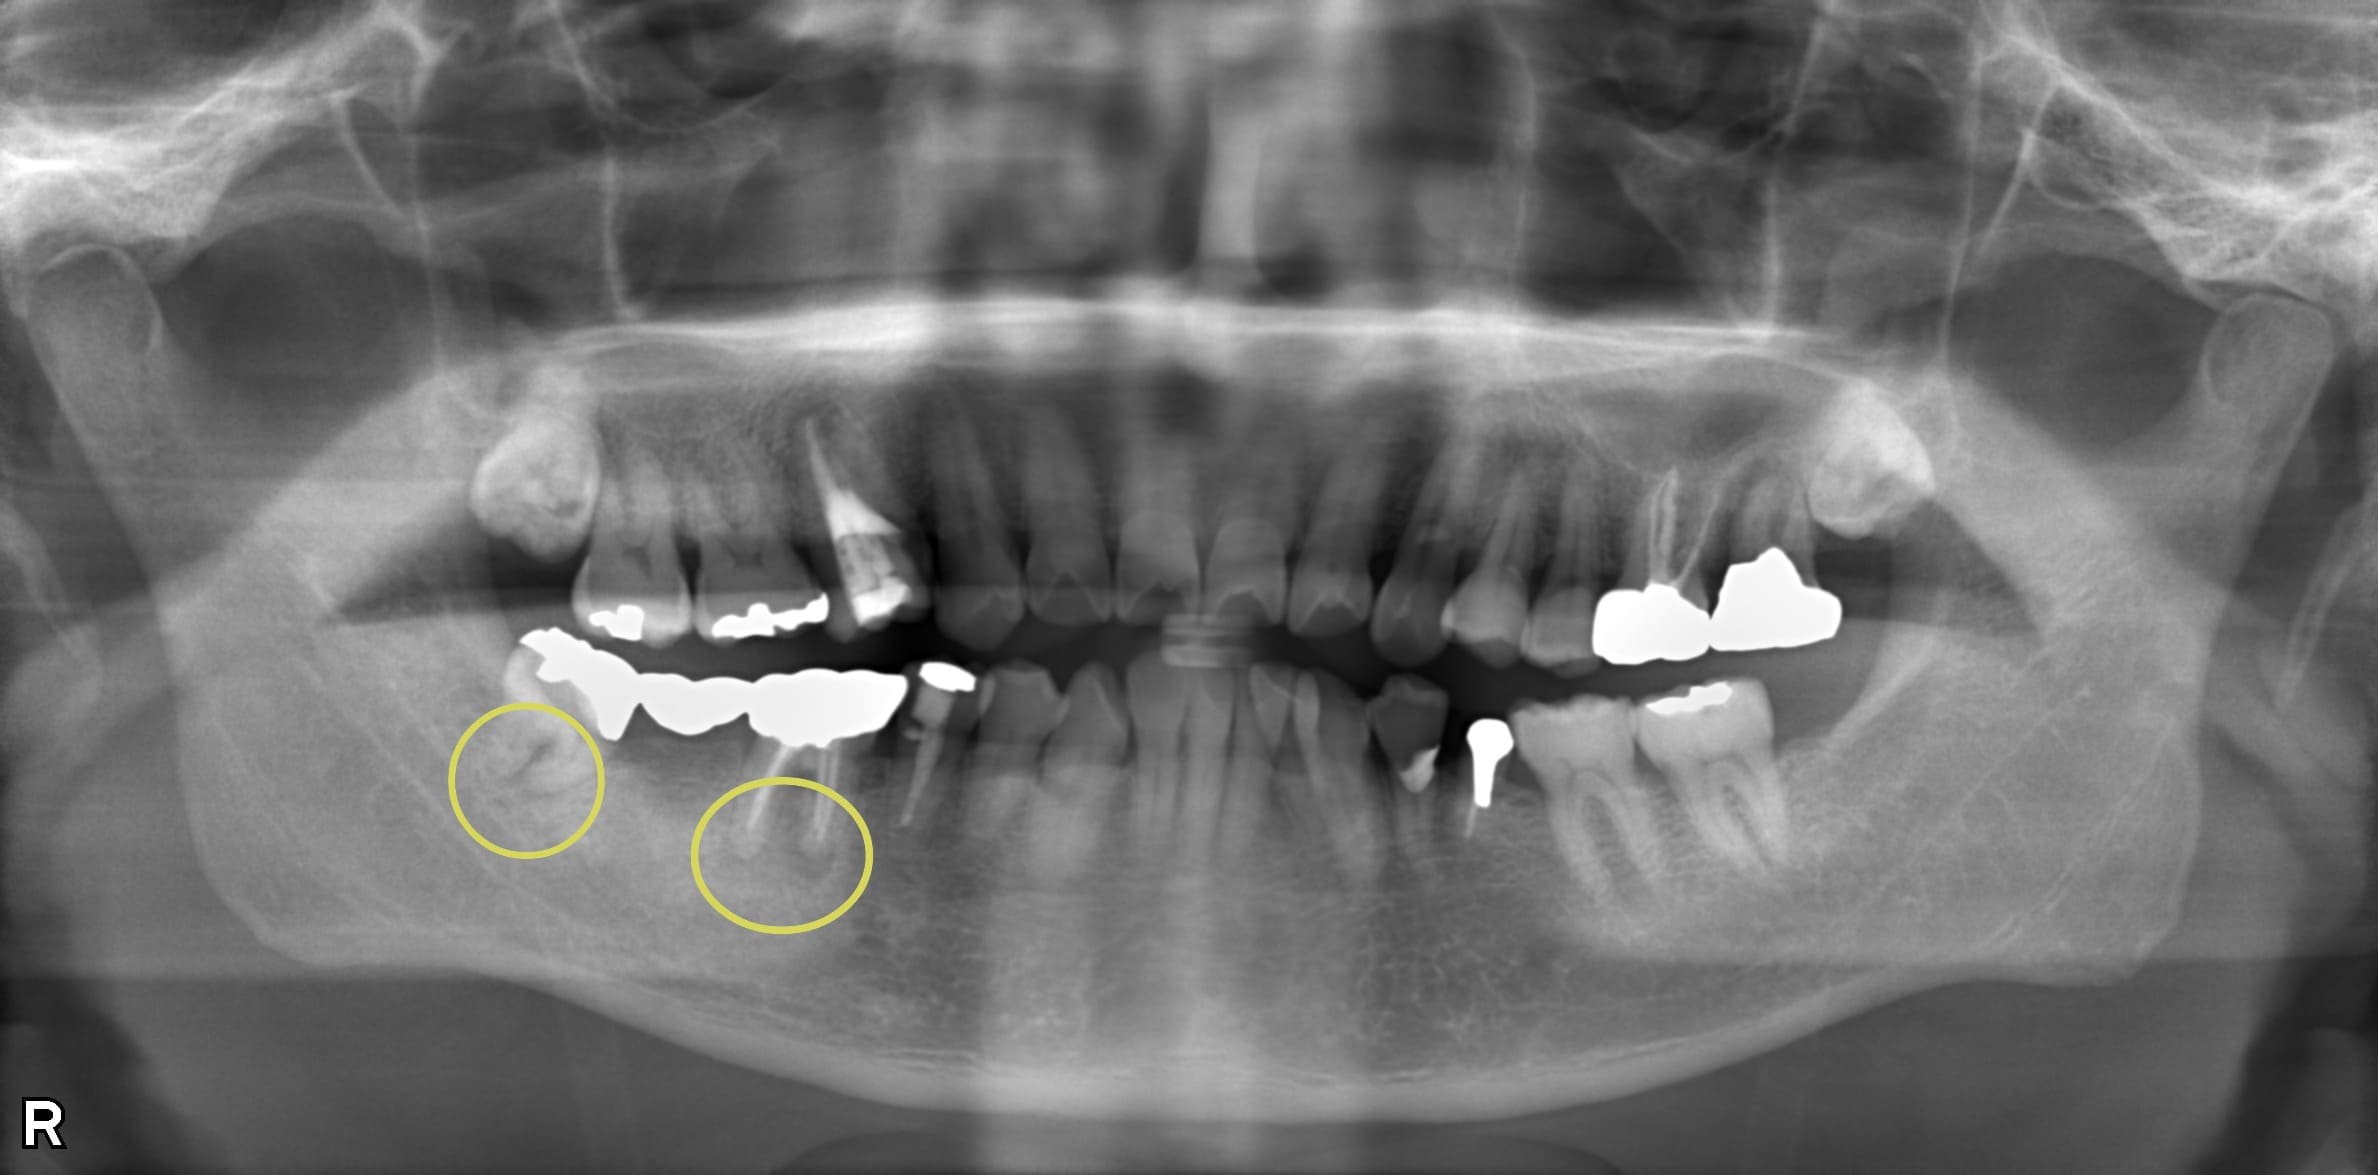

症例紹介